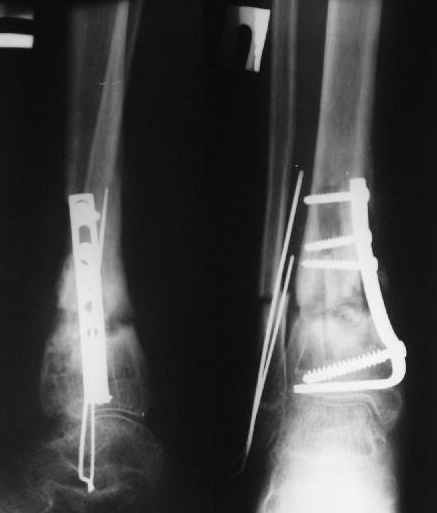

Перелом костей н\3 правой голени со смещением. Перелом большеберцовой кости можно охарактеризовать как компрессионно-оскольчатый.

Операции: 1 Клиновидная резекция на вершине деформации м\берцовой кости.

2 Тугоподвижный ложный сустав н\3 б\берцовой кости. Рубцы выполняющие пространство между отломками, канал проксимального отломка иссечены.

Одномоментное устранение деформации, остеосинтез Г-образной пластиной.

Пластика по Хахутову.